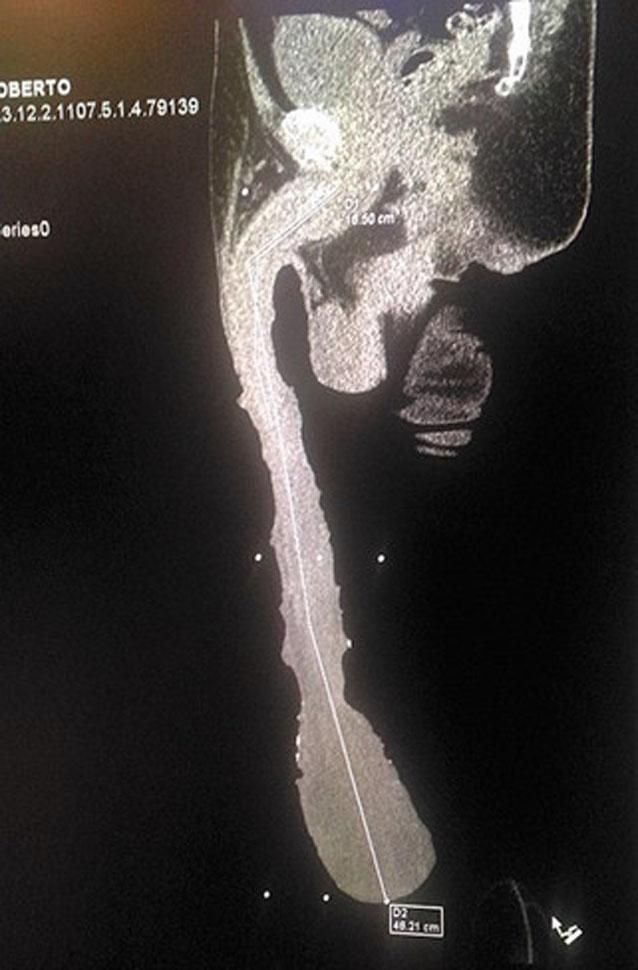

"Mire hasta dónde me llega, debajo de las rodillas. No puedo hacer nada, no puedo trabajar, soy un discapacitado". Con este argumento, el mexicano Roberto Esquivel Cabrera sostiene que no puede conseguir trabajo por tener un miembro masculino de 48,2 centímetros de largo.

La novedad fue dada a conocer por el periódico mexicano Vanguardia y Cabrera ahora pretende conquistar el récord Guiness como el ser humano con el pene más grande del mundo, título que hoy ostenta el neoyorquino Jonah Falco, con 34 centímetros.